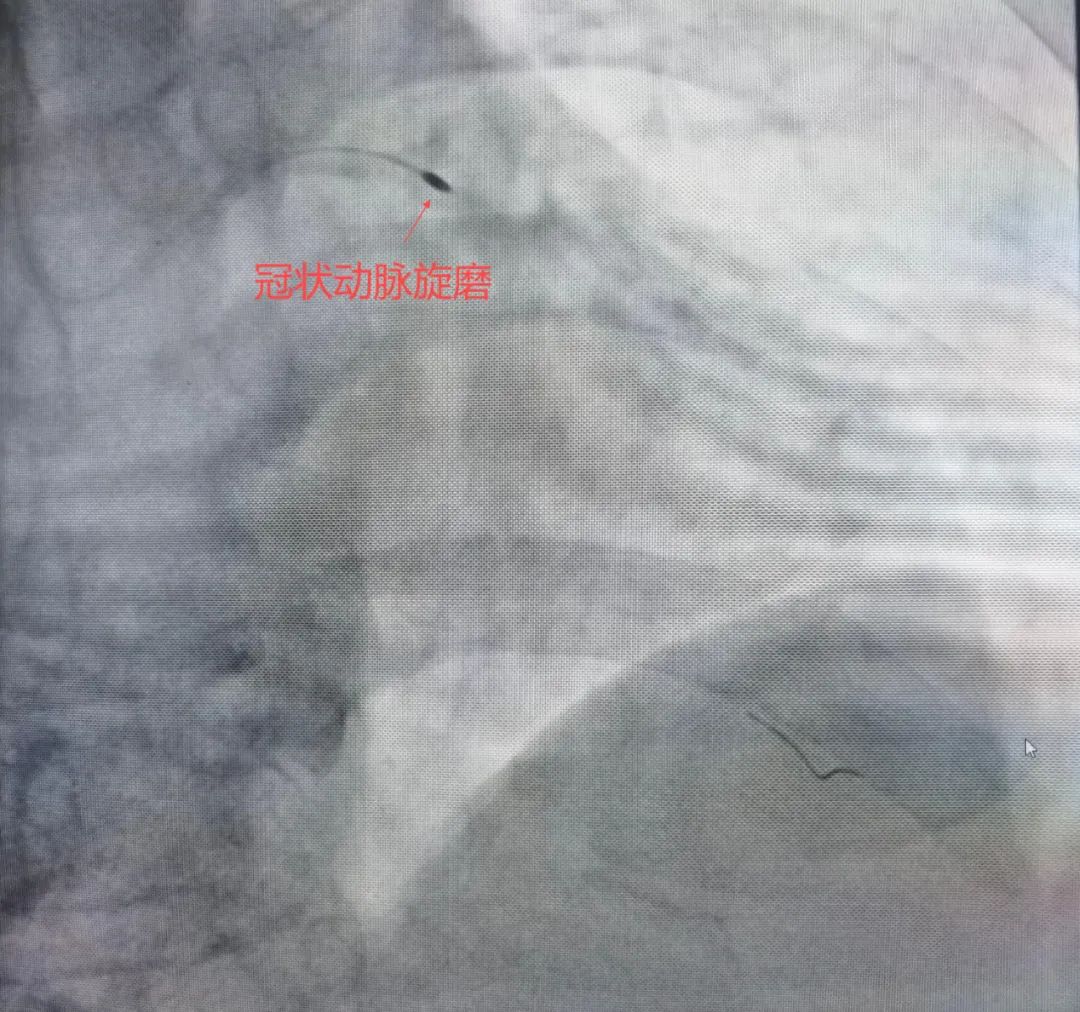

针对赵大爷的复杂病情,团队进行了充分术前讨论,决定采用“冠状动脉旋磨+冲击波球囊”的组合方案,最终成功置入支架,整个手术过程顺利,免除了患者外科开胸搭桥的痛苦。

冠状动脉钙化是老年冠心病患者的常见难题,重度钙化病变的介入治疗曾是临床“禁区”。旋磨术通过物理磨削打破钙化屏障,冲击波球囊则利用声波能量实现钙化斑块的高效碎裂,两者联合可显著提高手术成功率,减少血管损伤风险。该病例的成功实施,为高龄、高危冠心病患者带来了更安全有效的治疗选择。